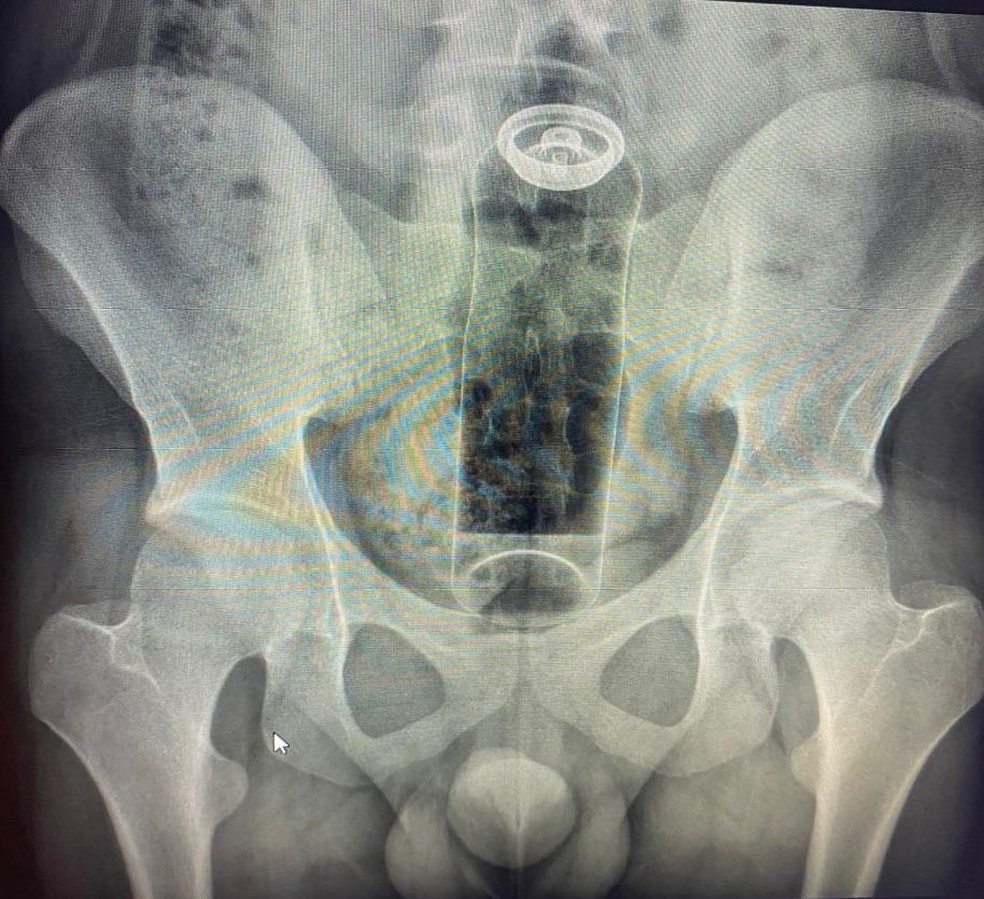

巴西一名19歲年輕男子,因在性行為中將止汗噴霧劑卡在直腸內而必須住院治療。

根據外媒報導,負責治療的直腸外科醫師丹尼爾(Daniel Brosco)表示,患者自述是在一次親密的性行為中,將止汗噴霧劑插入肛門,但該物品隨後被吸入直腸內,無法自行取出,最終必須接受醫院的醫療處置。